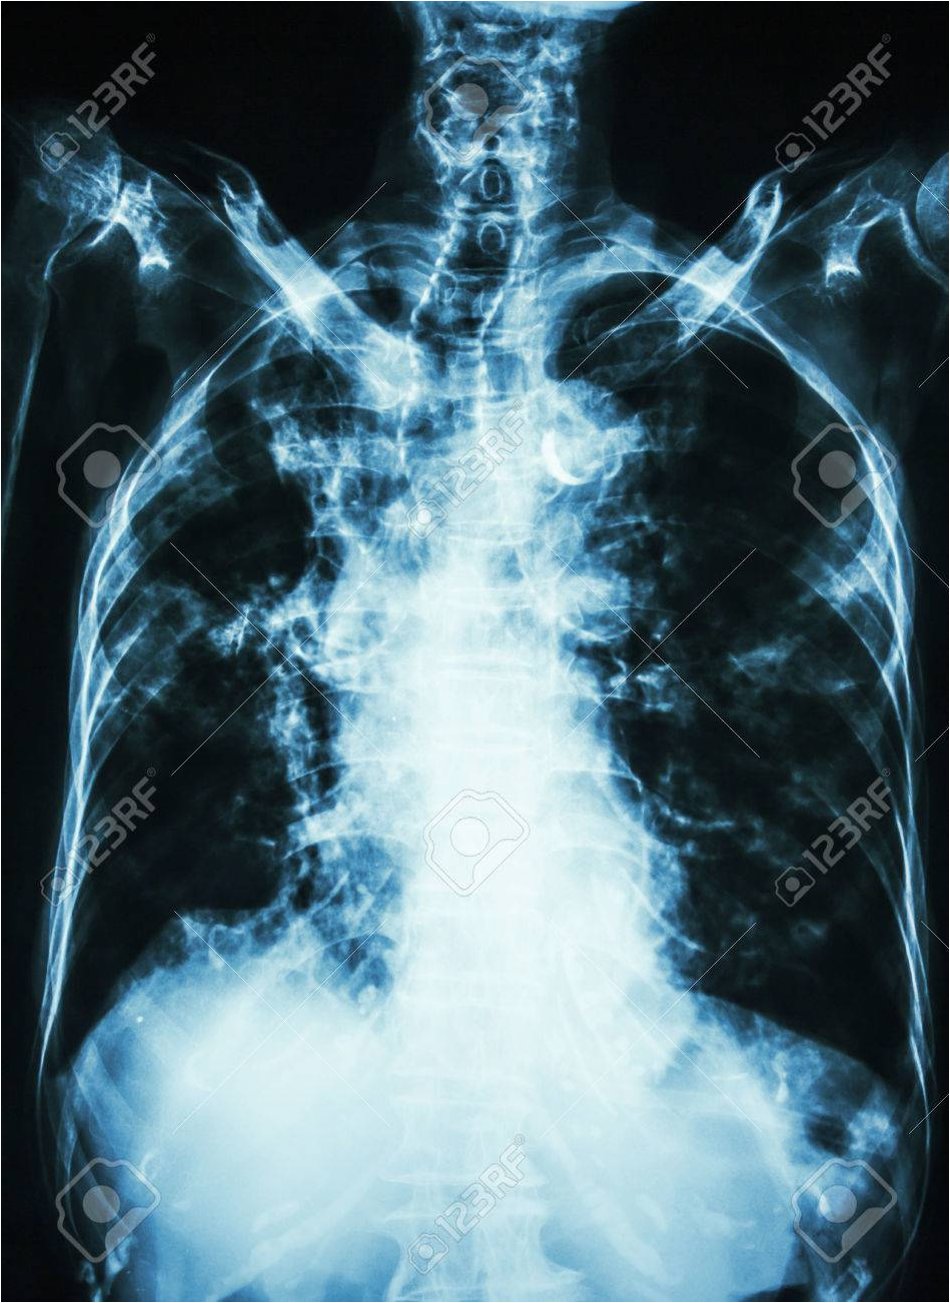

2019년부터 시작된 원인 불명의 밤마다 반복되는 고열로 병원을 찾은 사이먼스 씨는 CT 검사 결과 충격적인 사실을 마주했습니다. 사고 당시 폐 깊숙이 들어간 먼지 파편이 체외로 배출되지 못한 채 딱딱하게 굳어 왼쪽 폐 기관지를 완전히 막고 있었던 것입니다. 그는 “기계에 깔려 움직일 수 없을 때 먼지를 들이마셨는데, 그게 깊이 들어가 굳어버렸다”고 당시 상황을 설명했습니다. 의료진은 외상으로 인해 체내에 남은 이물질이 장기간에 걸쳐 칼슘으로 둘러싸여 석회화가 진행된 것으로 판단했습니다. 정밀 검사 결과, 좌측 폐는 5년간의 감염으로 기능을 완전히 상실한 상태였습니다.

의료진은 처음에는 석회화된 부분만 제거하려 했으나, 손상 범위가 너무 넓어 폐 전체를 적출해야 한다는 결론에 이르렀습니다. 사이먼스 씨는 결국 왼쪽 폐를 떼어내는 수술을 받았습니다. 그는 “작은 먼지 한 톨이 내 인생을 이렇게 바꿀 줄 몰랐다”며 “수술 동의서에 서명하던 순간이 인생에서 가장 무거웠다”고 심경을 토로했습니다. 이처럼 외상으로 체내에 남은 이물질은 장기간에 걸쳐 석회화되며 염증이나 조직 괴사를 일으킬 수 있습니다. 특히 폐 조직은 통증 수용체가 적어 초기 증상 인지가 어렵고, 뒤늦게 발견되는 경우가 많아 주의가 필요합니다.